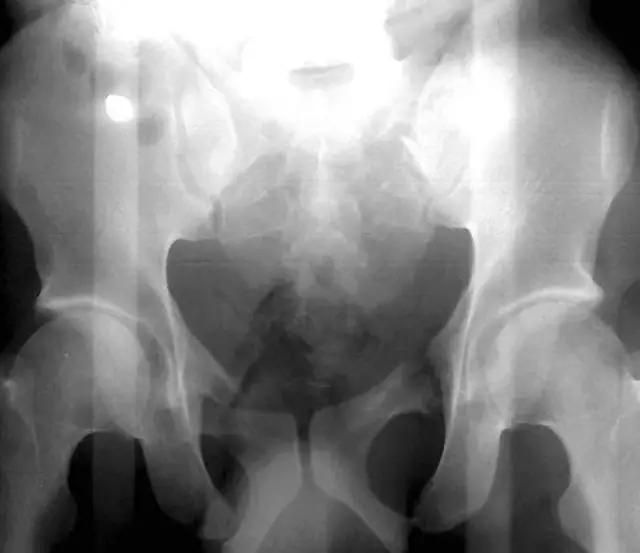

髋膝部骨折

1. Duverney 骨折

髂骨翼的骨折,但没有骨盆环的分离移位。

2. Malgaigne 骨折 (bucket handle 骨折,即桶柄骨折)

不稳定性骨盆骨折伴有前方和后方的骨折线累及髋关节。

3. Straddle 骨折

双侧耻骨上下支骨折。

4. Walther 骨折

经过耻骨支并延伸到骶髂关节的髋臼骨折。髋臼的内侧面向内移位。